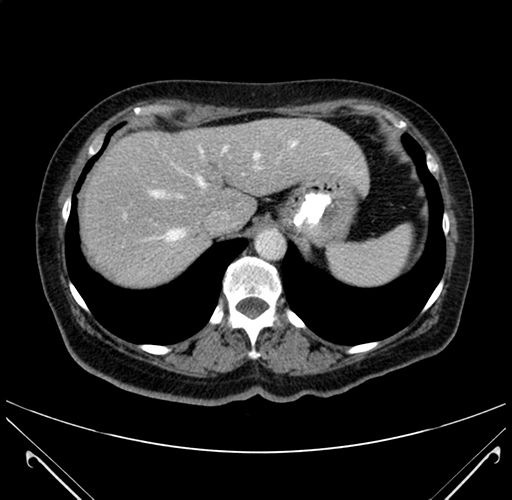

Pre-Chemo: Axial Venous

Axial Venous